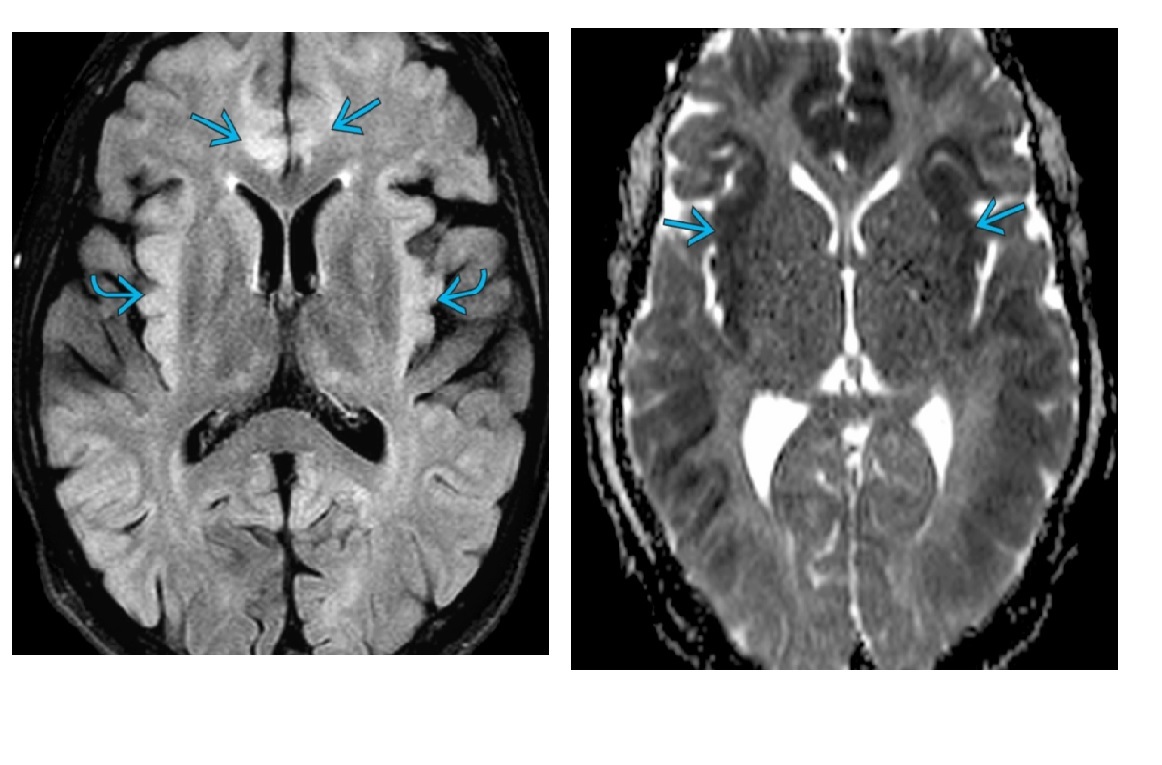

High T2/FLAIR on the dorsal medial thalamus, caudate lobe and putamina bilaterally with diffusion restriction?

A

CJD

Nb - called ‘ hockey stick’ sign

Also look for cortical gyriform restriction

WW3

C = caudate nuclei